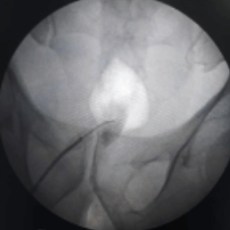

This procedure is performed with the patient in a prone position on the Operating table. Some practitioners like to prepare patients with laxatives the night before. With fluoroscopic guidance, a thin spinal needle is advanced through the sacrococcygeal hiatus. Needle placement is confirmed and dye spread is checked under fluoroscopy. Medication is delivered at the site of the Ganglion of Impar. This helps in blocking the sacrococcygeal plexus of nerves.

Lateral view

Intraop fluoroscopy image of ganglion impar injection